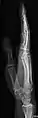

- استخوان رادیوس و اولنا - AP و جانبی

- مچ دست - DP و جانبی

تصویر مچ دست چپ به واسطه dorsoplantar

پروجکشن جانبی